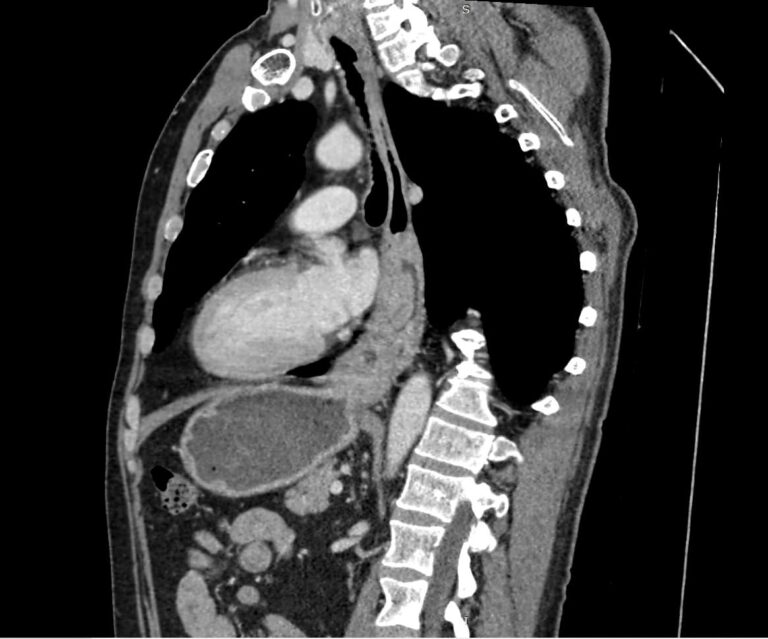

- опухоли – рак или доброкачественные новообразования (полипы, липомы, папилломы);

- кисты пищевода;

- врожденные пороки развития;

- инородные тела – в том числе те, которые вышли из пищевода в средостение (например, острые рыбьи кости);

- травматические повреждения пищевода;

- разрывы (могут быть не только травматическими, но и спонтанными);

- рубцовые сужения;

- свищи – патологические ходы, которые ведут в средостение или соседние органы, например в трахею;

- дивертикулы (выпячивания стенки пищевода);

- грыжи пищеводного отверстия диафрагмы;

- болезни оперированного и искусственного пищевода (слепой мешок, стриктуры, избыточная культя и т.д.).